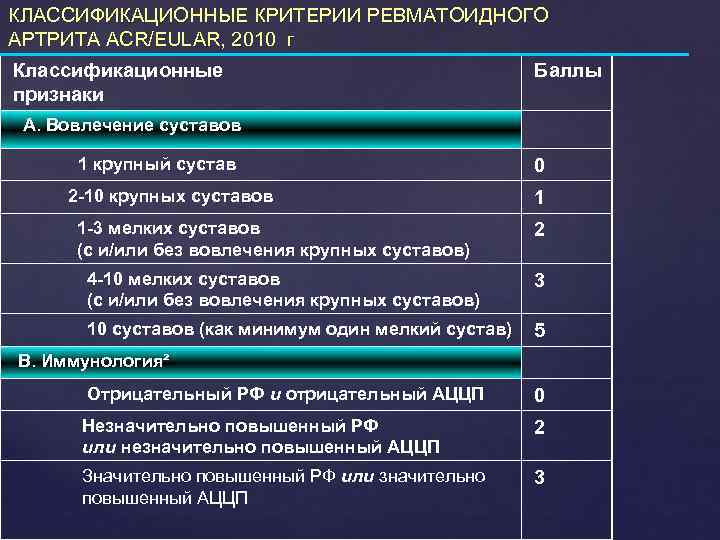

КЛАССИФИКАЦИОННЫЕ КРИТЕРИИ РЕВМАТОИДНОГО АРТРИТА ACR/EULAR, 2010 г Классификационные признаки Баллы А. Вовлечение суставов 1 крупный сустав 2 -10 крупных суставов 1 -3 мелких суставов (с и/или без вовлечения крупных суставов) 0 1 2 4 -10 мелких суставов (с и/или без вовлечения крупных суставов) 3 10 суставов (как минимум один мелкий сустав) 5 В. Иммунология² Отрицательный РФ и отрицательный АЦЦП 0 Незначительно повышенный РФ или незначительно повышенный АЦЦП 2 Значительно повышенный РФ или значительно повышенный АЦЦП 3

КЛАССИФИКАЦИОННЫЕ КРИТЕРИИ РЕВМАТОИДНОГО АРТРИТА ACR/EULAR, 2010 г Классификационные признаки Баллы А. Вовлечение суставов 1 крупный сустав 2 -10 крупных суставов 1 -3 мелких суставов (с и/или без вовлечения крупных суставов) 0 1 2 4 -10 мелких суставов (с и/или без вовлечения крупных суставов) 3 10 суставов (как минимум один мелкий сустав) 5 В. Иммунология² Отрицательный РФ и отрицательный АЦЦП 0 Незначительно повышенный РФ или незначительно повышенный АЦЦП 2 Значительно повышенный РФ или значительно повышенный АЦЦП 3